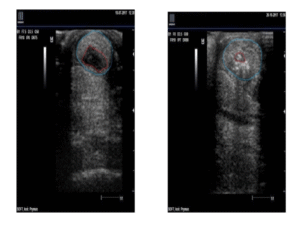

Regeneracja Uszkodzonych Ścięgien

Pulsacyjna terapia magnetyczna (PEMF) Biomag VET zyskuje stałe miejsce w minimalizowaniu urazów ścięgien u zwierząt sportowych. Mówimy o problemie kluczowym nie tylko dla wydolności, ale